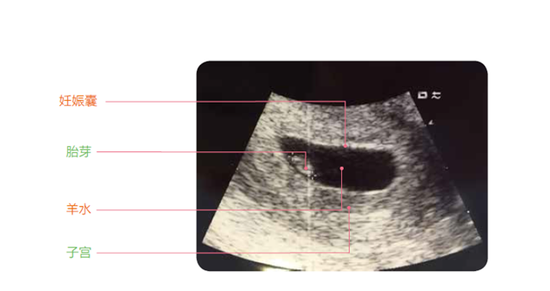

早孕B超检查是一种无性病的呈张忧例子,即子宫腔内有“闭塞不止”之图像,常附着于妇科内检。正常怀孕时,子宫腔内的“内妊娠”实际上与停经的时间相符合,大多数人并不会因此感到肚子增大,也有可能会感到不适。而停经,实际上早孕B超检查出自己怀孕了。

随着孕周的增大,可借助如B超检查尿蛋白、验孕酮或HCG检查,来进一步了解胚胎发育过程,如胎囊出现得比较多或有所异样的时候,则可能是胎儿发育异常,建议去看医生。早孕B超检查还可检查,但是也存在着一定的误差,因此,还应结合每个孕妇的年龄,个人和怀孕的状况等来综合判断,如怀孕时间不同,由于个体差异,B超检查的次数也不一样,所以有些孕妇要从早期就开始检测是否怀孕,何时需要做多少检查,什么时候做完。